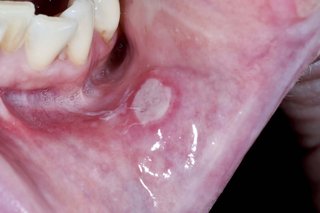

Check if you have a mouth ulcer

You may have more than 1 ulcer at a time.

Mouth ulcers are not contagious and should not be confused with cold sores.